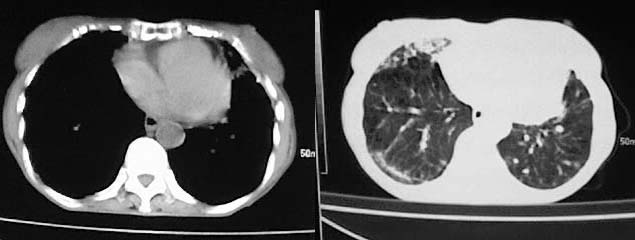

以下是引用有风的日子在2008-5-2 12:13:00的发言:[br][emb10][br][br]肺ca?有病理支持吗?[br][br]我看更象是肺tb并支扩、间质性肺炎。最好拿个病理结果来,不然这点影像资料诊断肺ca是难以服人的![br][br]至于主动脉瘤的诊断问题,国外认为≥4.0cm就可诊断了,国内对此诊断标准更为严格。患者升主动脉明显增粗,即>4cm。你诊断个升主动脉扩张并不为过!

以下是引用zjzjr在2008-5-2 14:39:00的发言:[br]支持双侧继发型肺结核,左侧胸膜肥厚,慢性支气管炎伴间质纤维化.